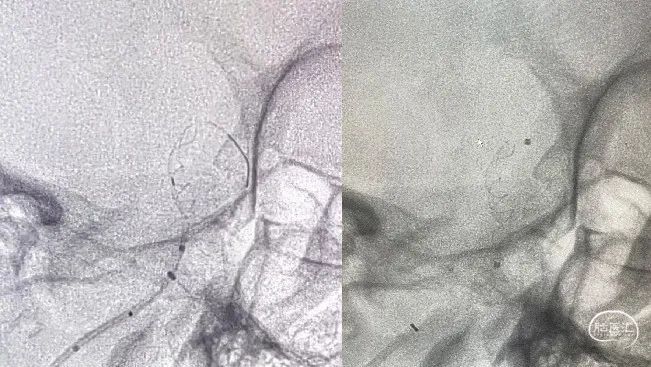

利用微导丝按摩支架。

术后即刻影像(正侧位):造影显示动脉瘤瘤内造影剂滞留,载瘤动脉、双侧大脑后动脉,小脑上动脉显影良好,逐次撤除支架微导管,中间导管,6F长鞘。